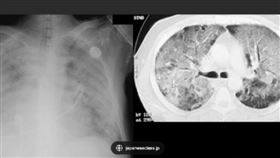

LDCT篩檢擬擴大 3肺病「優先納公費」

肺癌已擠下大腸癌,成為國內發生率最高的新癌王,為強化...

確診者驚見白肺 中國:與原始病毒株無關

中共迅速放寬防疫措施,讓各地恢復正常生活,然而造成的...

肺部纖維化不可逆 做到6件事能保命

新冠肺炎疫情仍在全球肆虐,不少人擔心的除了生命安危之...

「菜瓜布肺」死亡率高!我國研究有解

肺部纖維化,也就是俗稱的「菜瓜布肺」,為不可逆疾病,...

65歲翁咳、喘、累 聽診揪出菜瓜布

聽診竟也有撇步?聽診器對正後背下肺葉,不怕菜瓜布肺悄...

爬樓梯、走路喘不停 小心菜瓜布肺

以前可能可以爬三、四層樓的人,發現現在只能爬一、兩層...